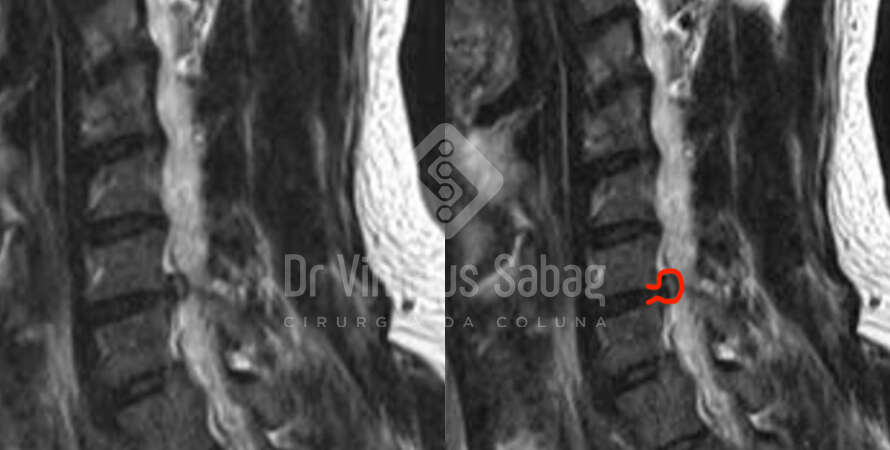

O diagnóstico geralmente é feito por meio de avaliação clínica e exames de imagem, como ressonância magnética, que permite visualizar o estado dos discos intervertebrais e possíveis compressões nervosas.